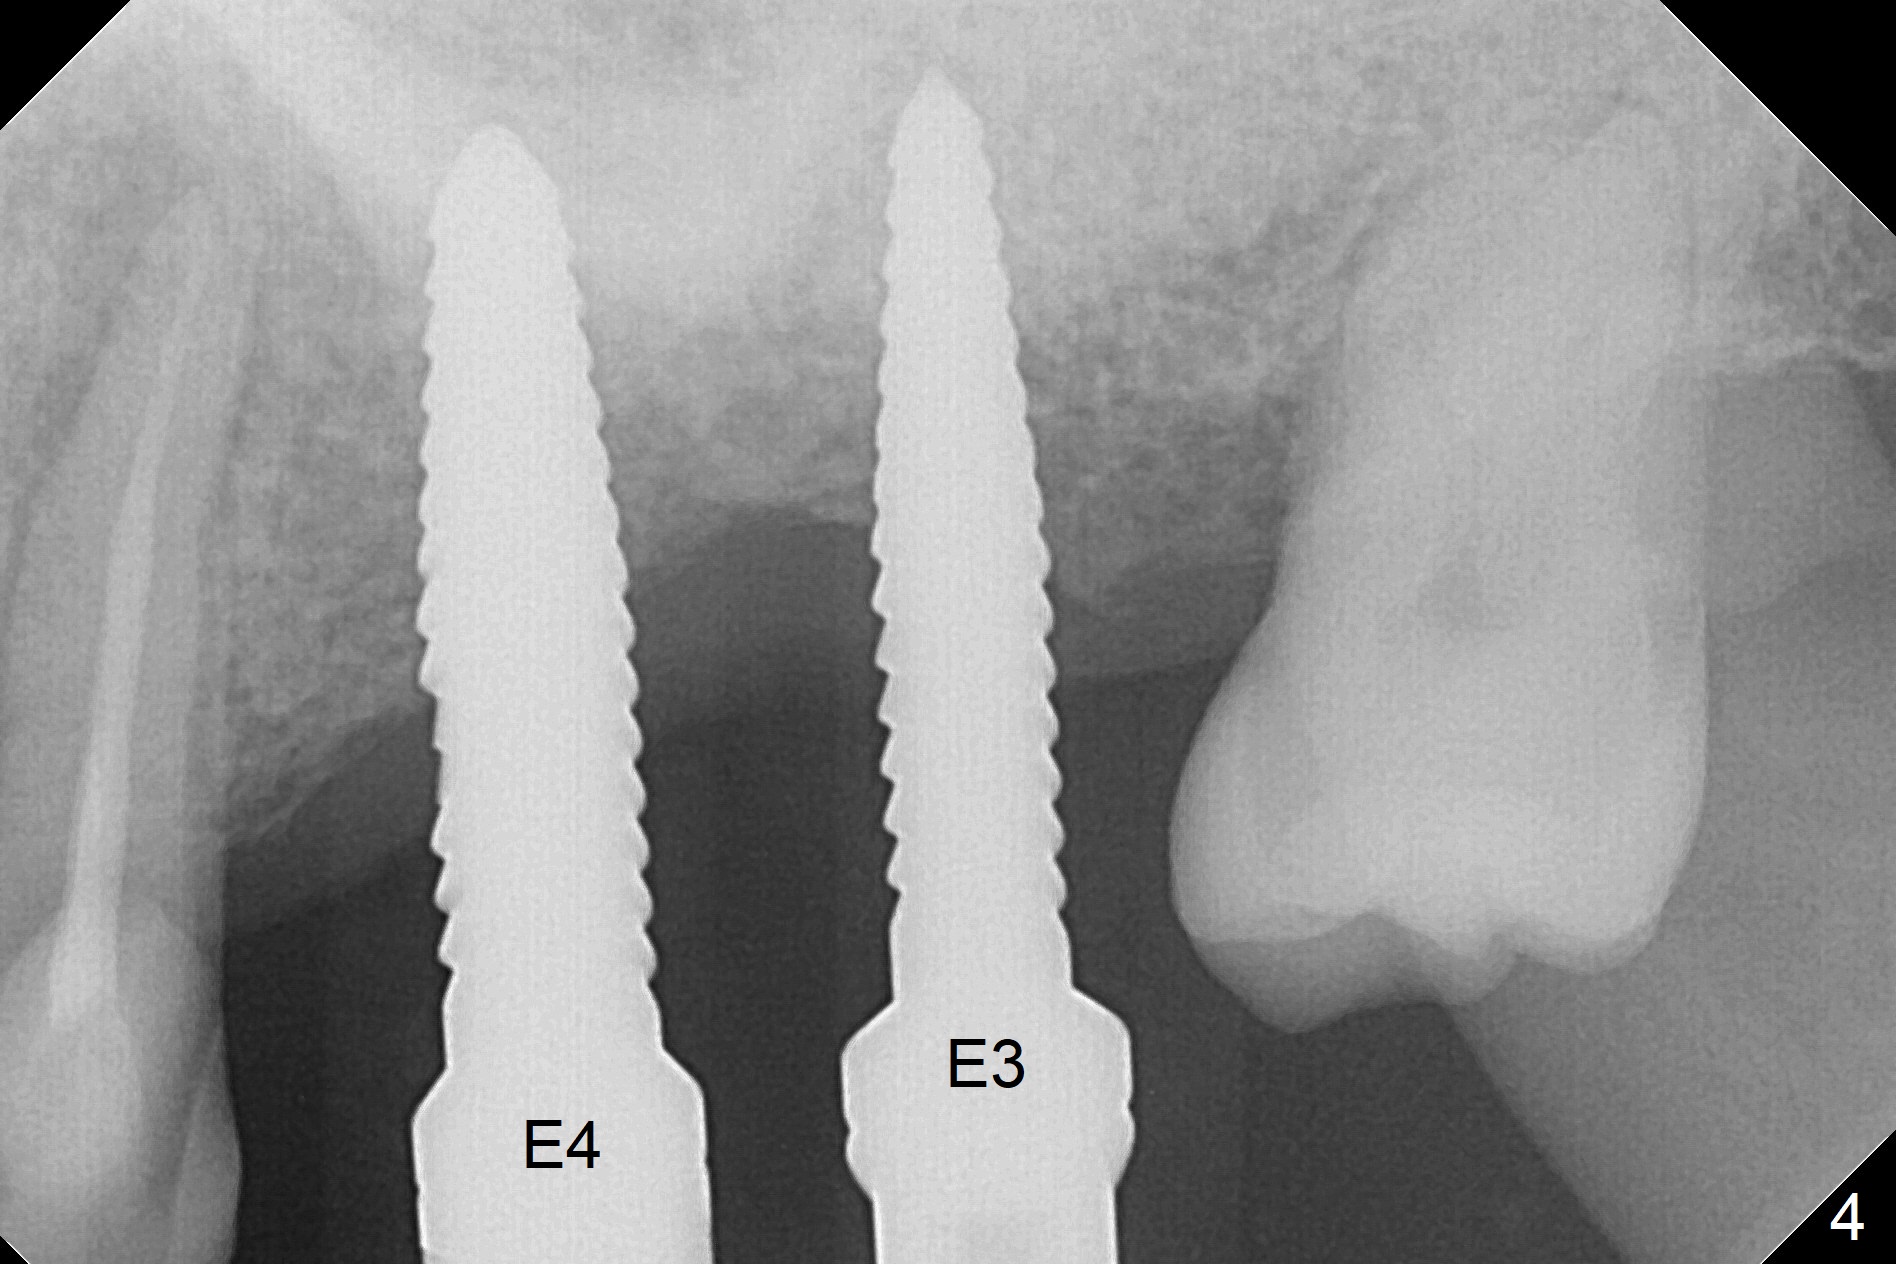

When 1.2 mm drill is used for osteotomy at #14 and 15, the bone feels to be soft (Fig.1). After change in trajectory (Fig.2), Expander 1 (Fig.3: E1, 1/1.6 mm) can be inserted at #14 and 15, while E2 (1.2/2.3 mm) cannot at full length at #14, suggesting hard bone. Osteotomy continues with drills until 4.1x14 mm, followed by insertion of E4 (2.4/3.7 mm) at #14, while osteotomy goes on until E3 (1.7/3.1 mm) at #15 (Fig.4). A 4.5x12 mm SM implant is placed with 50 Ncm (with insertion of a 5.8x4(2) mm abutment as a guide for #15 osteotomy, Fig.5). The apical portion of the osteotomy at #15 (Fig.5 red line) is finished with drills, leading to placement of a 4.5x12 mm implant (>50 Ncm) and 4.8x4(2) mm abutment (Fig.6). With bone density is more than 200 units, bone expansion appears to be not indicated. The patient returns for #13-15 crown prep 4.5 months postop (Fig.7). Abutments change to 5.8x5(3) and 5.8x4(3) mm at #14 and 15, respectively with mesial reduction of the tooth #16 (curved line) before impression. Minimal bone loss is observed 1 year 5 month post cementation (Fig.8,9), thanks to pre-existing wide bone.